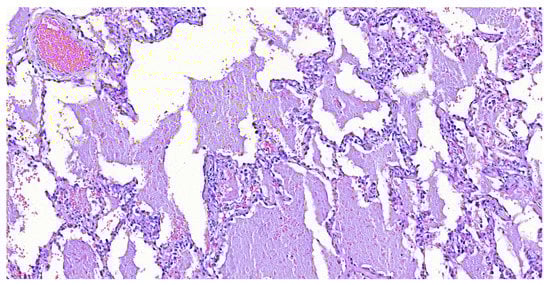

Alveolar Proteinosis Secondary to M. tuberculosis, in a Patient with Transient CD4 Lymphocytopenia Due to Cryptococcus neoformans Infection: First Case in the Literature

2. Case Report